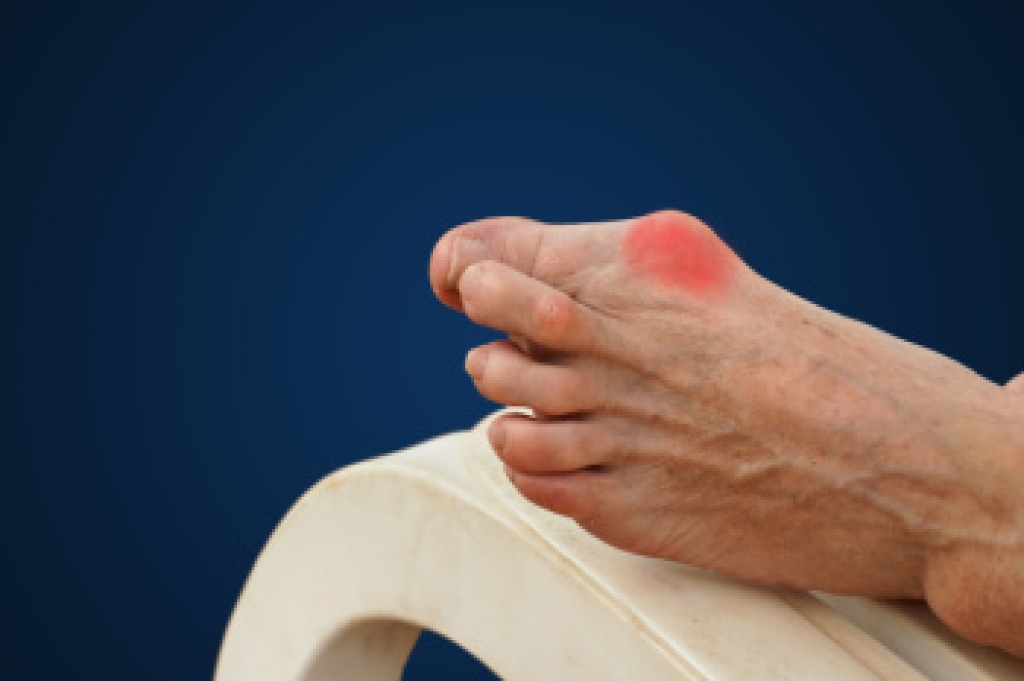

Working on your feet for long hours can lead to a variety of foot-related issues. The constant stress on the bones, muscles, and tendons can cause inflammation, pain, and even permanent structural changes. The foot's arches, which normally act as shock absorbers, may weaken due to prolonged standing or walking, leading to flat feet. This loss of arch support can affect not only the feet but also the knees, hips, and lower back, making them more vulnerable to injury. Painful foot conditions related to working on the feet include plantar fasciitis, Achilles tendonitis, and bunions, all of which may worsen with time. Symptoms like fatigue, pain, and discomfort often spread from the feet to the legs and back, making it difficult to continue standing or walking for extended periods. If you have foot pain related to working on your feet, it is suggested that you make an appointment with a podiatrist for an exam, diagnosis, and treatment options.

Standing on your feet for long periods of time can cause stress and pain in your feet. Your whole body may experience change in terms of posture, back pain, bunions, callouses and or plantar warts. There are ways to avoid these conditions with proper foot care, smart choices and correct posture.